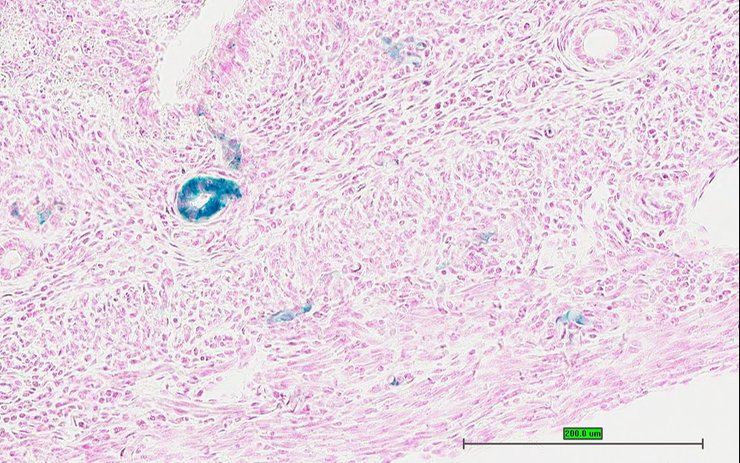

TS28: skin Present UC Davis_1872986

Specimen UC Davis_1872987: postnatal adult; Ch25htm1.1(KOMP)Vlcg/Ch25h+ (more )

Structure Level Pattern Image Note

TS28: skin Present UC Davis_1872987

TS28: skin Present UC Davis_1872943

Specimen UC Davis_1872944: postnatal adult; Ch25htm1.1(KOMP)Vlcg/Ch25h+ (more )

TS28: skin Present UC Davis_1872944